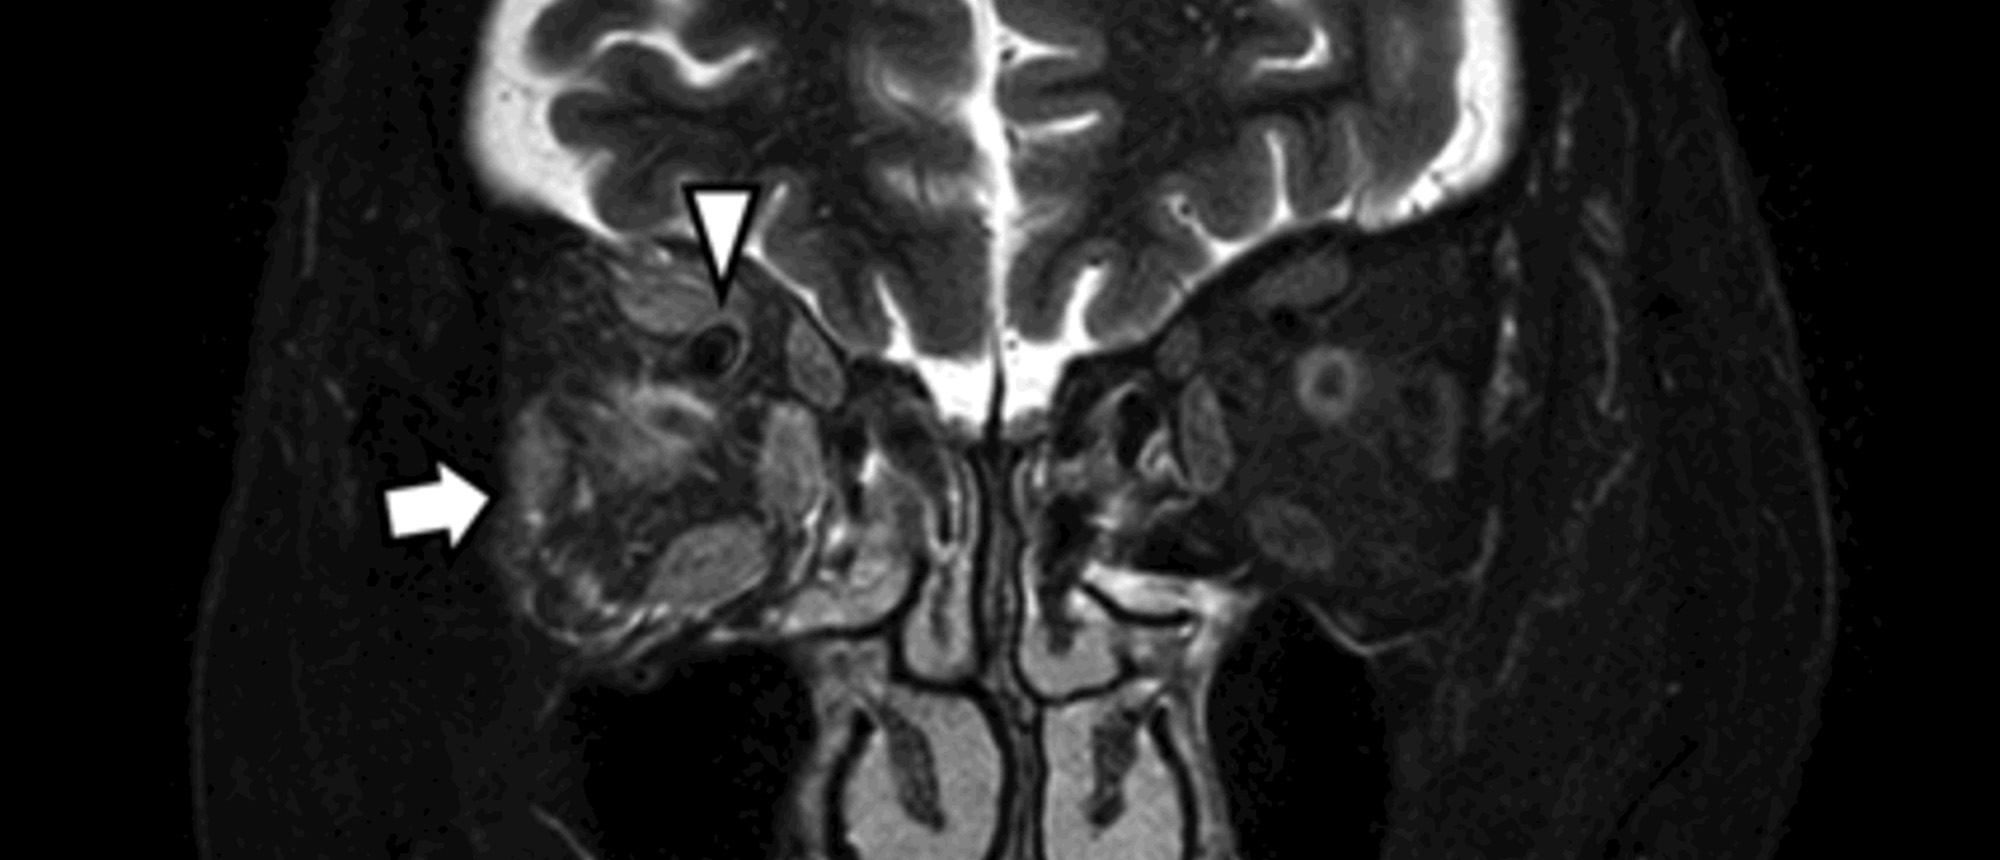

Orbital Rhabdomyosarcoma - Recurrence A young patient with notable past ocular history of orbital rhabdomyosarcoma, s/p chemotherapy with vincristine, dactinomycin, and cyclophosphamide, and proton beam radiation presented to Bascom Palmer ED with 2 days of blurry vision and “seeing everything gr…